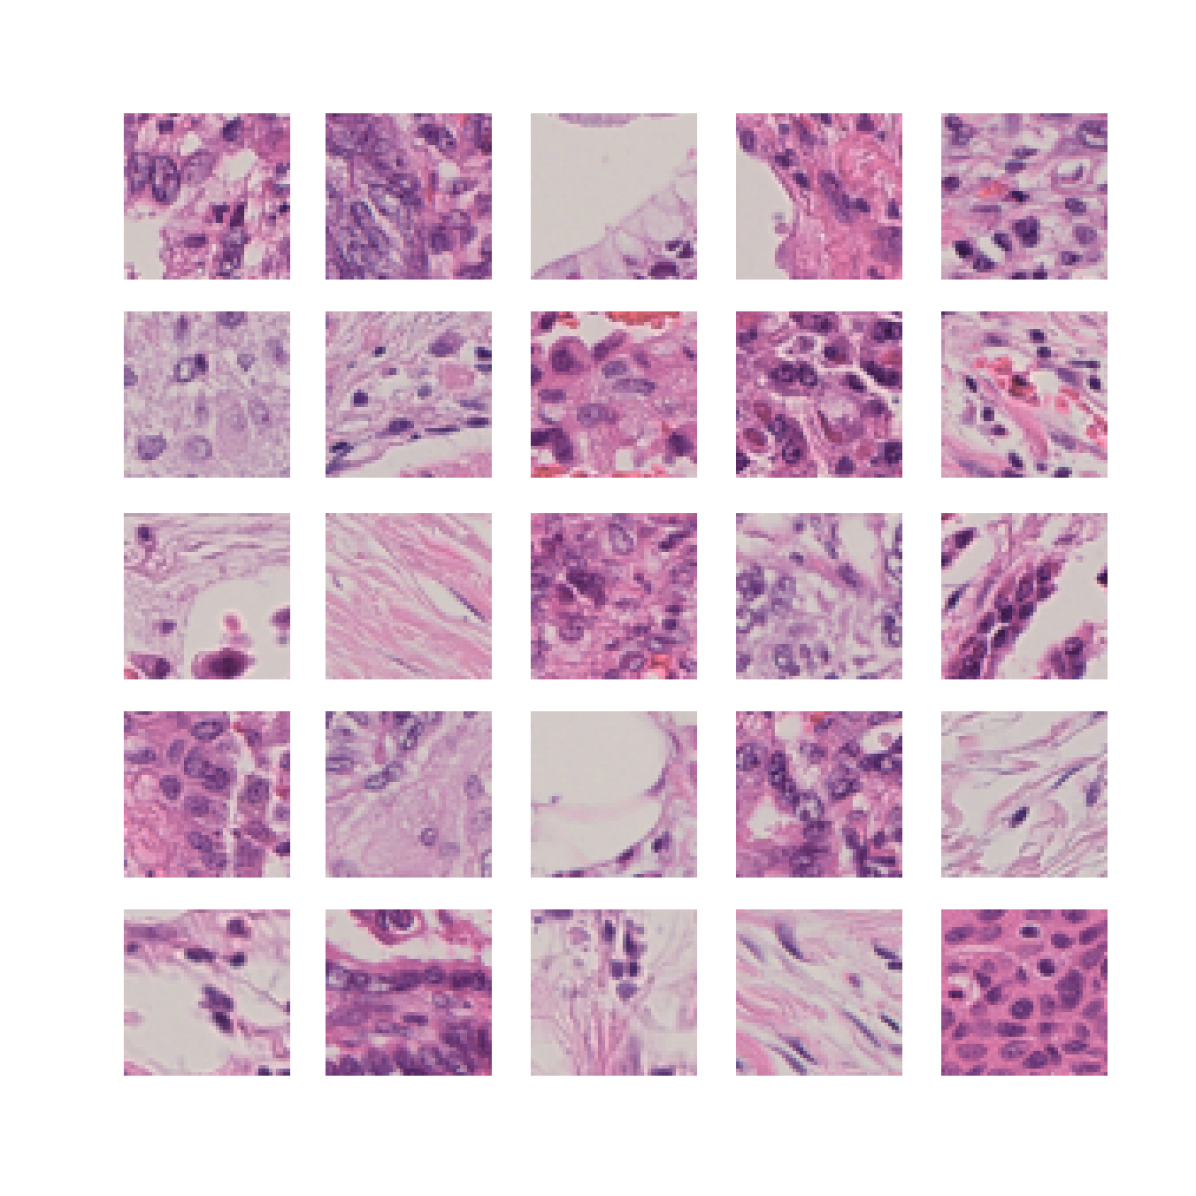

We also analyse the activation maps for each model using GradCAM as described in section S3. This offers more insight into the areas of the image which are contributing most heavily to the models’ representations. In Figure 4(b) we present some representative examples, however, a larger selection which was chosen at random is presented in Figures S10 to S25. The larger selection makes it easier to see the emergent patterns, including that privileged Siamese models tend to mainly identify features which are strongly present in both inputs, while unprivileged Siamese models tend to learn more diffuse features that are not specific to one cell phenotype or image region. TriDeNT ♆ incorporates both sets of features, learning both features specific to the privileged data and more the general features associated with unprivileged Siamese networks.

We can see in Figure 4(b) panel A that for ERG, the privileged Siamese model focuses almost exclusively on any nuclei which could be endothelial cells. As there are very few endothelial cells in the dataset, it could be an effective strategy to identify anything that could potentially be an endothelial cell to minimise the difference between the representations of the H&E model and the IF mask model. In the corresponding unprivileged Siamese image, we see that the model identifies some of these nuclei, albeit less strongly, but also focuses heavily on the other tissue and even the background, while strongly fixating on two spots of debris in the center of the image. This model has less ‘incentive’ to learn the weak features related to endothelial cells as these occur rarely and are not easy to detect, while more generic strong features such as the presence of connective tissue and the prevalence of background are more common and predictable from augmented images. We see that TriDeNT ♆ combines these two feature sets, strongly identifying nuclei while also identifying the connective tissue.

In panel C we see a similar pattern, with the privileged Siamese model fixating solely on the nuclei, while the TriDeNT ♆ model takes a more balanced approach. The unprivileged Siamese model appears to focus on a single cluster of nuclei while neglecting others, and similarly identifies an area of fibroblasts with its distinctive pattern but does not others.

In contrast to panels A and C which represent models with poor privileged Siamese results, panels B and D represent models whose privileged Siamese results were comparable to both TriDeNT ♆ and even the supervised baseline. It is therefore interesting to note that there are far more similarities between the privileged Siamese and TriDeNT ♆ models in both cases. Particularly in panel B, TriDeNT ♆ and the privileged Siamese model return virtually identical heatmaps, with both strongly identifying epithelial nuclei and neglecting the same areas of connective tissue. The unprivileged model in this case appears to focus solely on the centre of the image, giving a significantly different heatmap to the other panels.

Panel D again shows the previous pattern, with the privileged Siamese model identifying the features strongly present in the privileged data – fibroblasts – while neglecting the nuclei present. TriDeNT ♆ also strongly identifies the connective tissue, but, unlike the privileged Siamese model, does not completely neglect the nuclei. The unprivileged Siamese model primarily identifies background, and does not appear to identify the nuclei in this example.